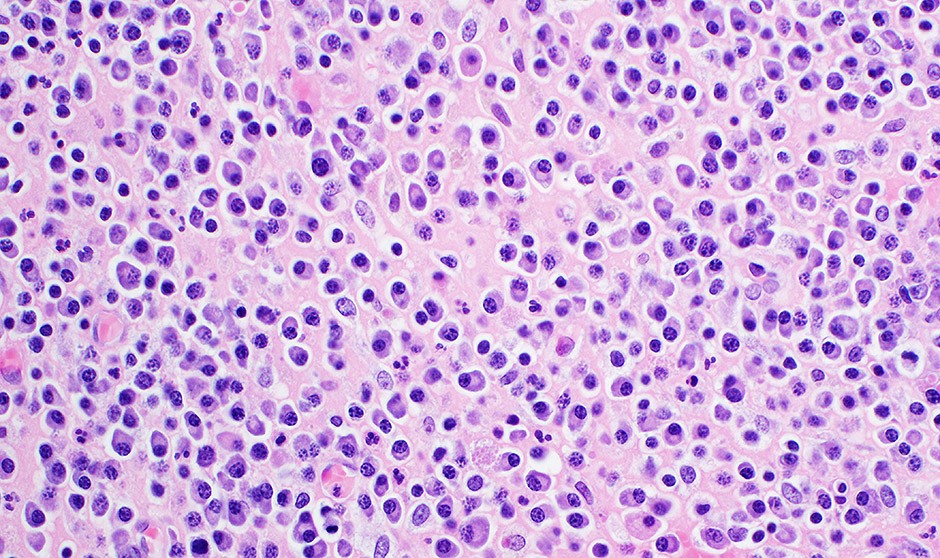

Micolactona, altamente tóxica para las células de mieloma múltiple

la micolactona es altamente tóxica para las células de mieloma múltiple, incluidas aquellas que se han vuelto resistentes a los inhibidores del proteasoma, en dosis que no son tóxicas para las células normales.